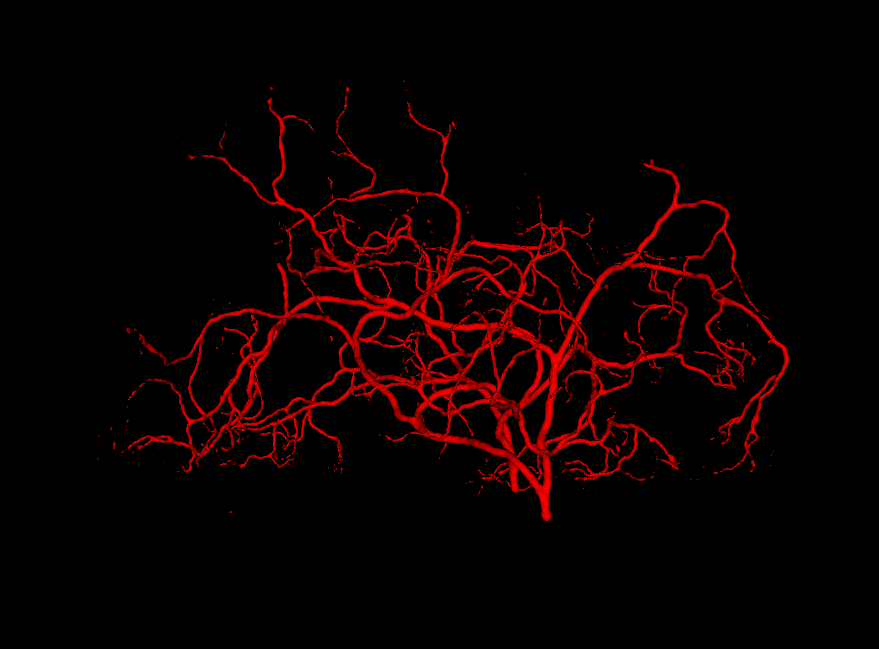

Refer to caption

Figure 3.2: Generated vessel structures with no spatial target growth incentive. The right figure was grown in a small spatial volume relative to the root width, while the left was grown unconstrained by volume.

Figure 3.3: Generated vessel structures with spatial target growth incentive. The target volume was a vessel density atlas created by averaging the ground truth of patients in our data set.

Another use of the vessel atlas is to determine if a node is out of bounds. This is done by checking if the atlas has a value of 0 at the node’s position. If a leaf node is too far out of the brain, the branch is discontinued (the leaf will never be selected to spawn a child). On top of this, in order to make the overall structure more realistic, a different atlas was used for each of the two hemisphere root nodes. Such atlas would only have non-zero values for one brain hemisphere. This causes the resulting vessel structures to no longer cross over between hemispheres. A resulting example structure can be seen in Figure 3.3.